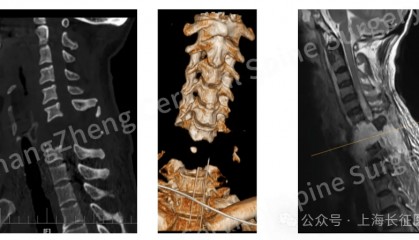

全球罕见!“身首离断”患者被救回 主刀医生:术毕两月整,已脱离呼吸机半月

8月18日,海军军医大学第二附属医院(上海长征医院)对一例“身首离断”式的罕见严重颈椎骨折脱位的患者...

全球罕见!中国医生救回“身首离断”患者

从业近30年,上海长征医院颈椎外科病区主任陈华江教授接诊过无数凶险的颈椎外伤患者,但称得上是“身首离...